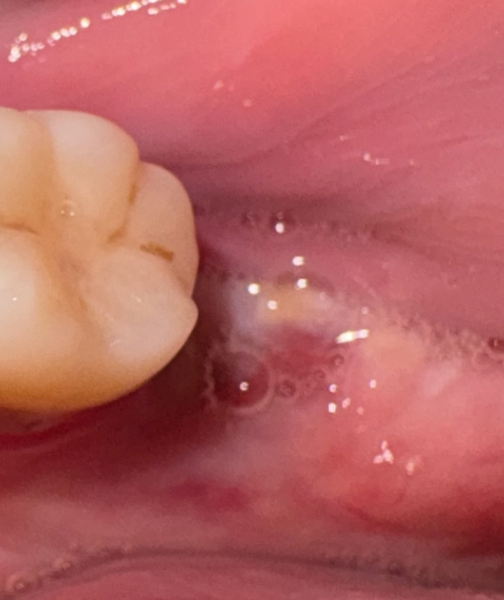

Hoping there are some dentists on here who can advise if this is healing ok? I am still pretty sore and achey after having my lower molar out on Sunday, now Thursday and pretty sore and painful. Unsure if it looks ok? Thank you

Looks great! No sign of infection, healing well, very clean.

Honestly it'll take 3/4 weeks for it to feel normal.

This is today, so the white is normal? Thank you x

Is it normal for the white to have disappeared since this morning?